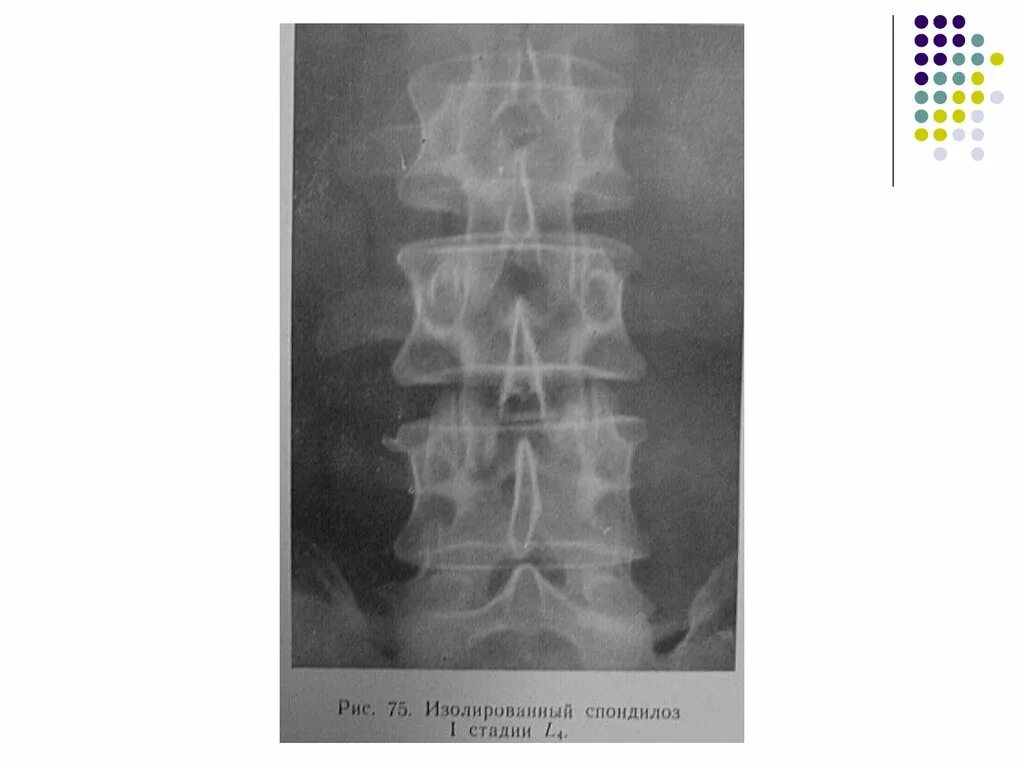

Краевые костные разрастания позвоночника